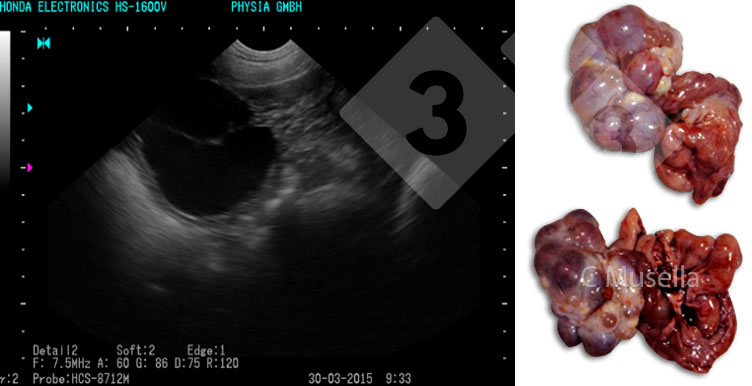

Figura 1. Corpo lúteo